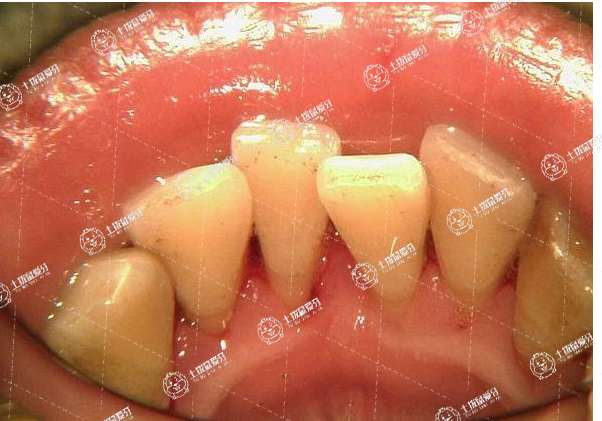

黑三產(chǎn)生最主要的一一個原因是牙齒清潔不到位,牙齒矯正中由于鋼絲、托槽的存在,使得牙齒清潔困難,還會有很多清潔死角,單靠牙刷是很難達到全面清潔牙齒的目的。清潔不到位的牙齒表面會附著菌斑,產(chǎn)生牙結(jié)石。牙齦血液循環(huán)不足加之受到牙菌斑牙結(jié)石分泌的物質(zhì)的影響時,容易導(dǎo)致牙齦萎縮而產(chǎn)生黑三角。

很多人在進行矯正前的牙齒是深覆合、深覆蓋、擁擠等情況的,在進行矯正排齊后,于排開了牙齦露出了,也容易出現(xiàn)黑三角。